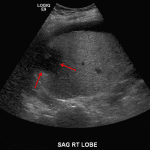

- Heterogeneous hypoechoic lesion in the periphery of the right hepatic lobe measuring up to 5.5 cm without internal vascularity

- Small volume, heterogeneous appearing perihepatic fluid

Heterogeneous hypoechoic lesion in the periphery of the right hepatic lobe measuring up to 5.5 cm without internal vascularity, concerning for an abscess. Adjacent small volume complex ascites raises concern for intraperitoneal rupture.